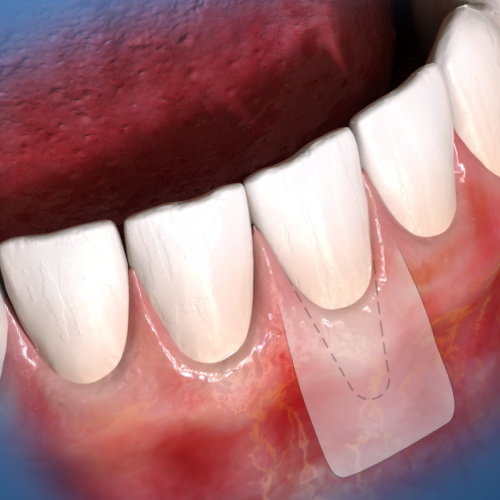

Oral Surgery Novelties

Monday, September 11, 2023

This Compendium eBook features a continuing education (CE) article on the treatment of peri-implant soft-tissue dehiscences (PSTDs), an esthetic complication of implant surgery. This eBook also includes a case report article on the use of coronectomy to treat complicated full-bony impacted ...

Oral Surgery Advances

Friday, September 16, 2022

This Compendium eBook offers a continuing education (CE) article that examines how clinicians can enhance biopsy techniques with the use of a dental laser. Also included in this eBook is a case report article, highlighting two case studies, on the use of a crosslinked collagen membrane in c...

Oral Surgery Solutions

Friday, May 6, 2022

This Compendium eBook offers a continuing education (CE) article that discusses techniques that have been shown in studies to reduce the initial pain patients may experience with the injection of local anesthetics. A case report article is also highlighted in this eBook, describing the use ...

Innovations in Dental Esthetics

Sunday, April 12, 2020

This Compendium eBook provides a continuing education (CE) article on the esthetic and technical role of the abutment and a CE article on the problem of gingival recession in dental esthetics.

Innovations in Periodontics

Friday, January 31, 2020

This special Compendium eBook provides two continuing education (CE) articles to assist practitioners and their teams in understanding classifications for diagnosis that will lead to optimum patient care.

Spotlight on Oral Surgery

Wednesday, September 25, 2019

This special Compendium eBook puts the spotlight on two topics in oral surgery: papillae-sparing incisions and surgical complications from dietary supplements. Each topic is explored in a continuing education (CE) article.

Today's Trends in Periodontics

Monday, January 28, 2019

This special Compendium eBook brings you two continuing education (CE) articles on topics in periodontics. The first article explores the use of tuberosity connective tissue for root coverage and ridge augmentation. The second article describes extraction site preservation using a graft mat...

Advances in Periodontics

Wednesday, October 31, 2018

Advances in periodontal tissue regeneration and periodontal health assessment are topics featured in this special Compendium eBook, with two continuing education (CE) articles. The eBook also includes a case report on an edentulous patient.

Current Topics in Periodontics

Wednesday, April 25, 2018

This eBook provides two continuing education articles on periodontics, specifically on the topic of root coverage. In the first CE article, the author reviews and differentiates the therapies used to treat gingival recession and areas of deficient attached gingiva. In the second CE article, the auth...

Periodontal Maintenance

Monday, July 24, 2017

This special Compendium eBook focuses on combating peri-implant disease maintaining good tissue health and enhancing esthetics. The first article describes ways in which peri-implantitis is diagnosed and how to evaluate levels of risk as a means of preventing onset of this disease. A second article...

Periodontics

Monday, May 22, 2017

This special Compendium eBook describes a successful CO2 laser vestibular extension procedure performed in a patient with a chromosomal abnormality. It also presents a thorough classification for extraction sockets of single-rooted teeth, while providing guidance to clinicians i...